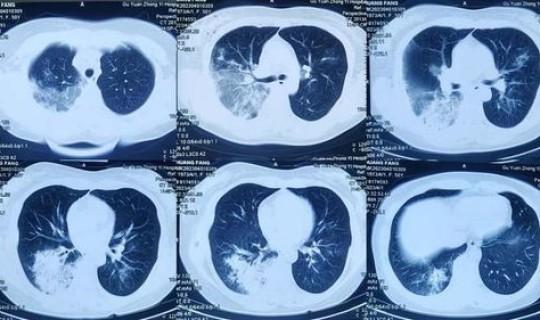

随着症状的加重 ,病人会出现呼吸困难、胸闷、气短,甚至会出现呼吸窘迫等严重症状 。进行影像学的检查会发现肺部有磨玻璃一样的肺间质的改变。表现严重的还会出现脓毒血症、感染性休克 、凝血功能障碍和肾功能衰竭等。